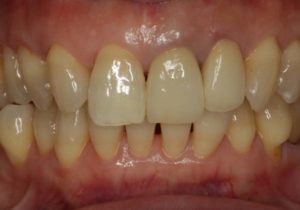

どのように変わったか、下の写真をご覧ください。

- 術前

- 術後